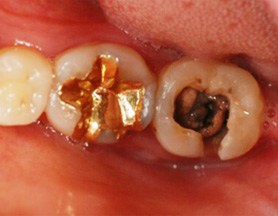

1년전 다른 치과에서 보철치료를 받은 부위에 지속적인 통증과 잇몸 염증으로 내원, 기존 보철물 수복시 신경관을 제대로 치료하지 못하여 염증이

재발된 상황이었습니다. 고운미소에서는 기존 포스트를 제거하고 오염된 부위에 약재를 삽입하여 염증을 제거하는 신경치료를 시행하였습니다.

기존 포스트 제거 후 근관내 약재 삽입